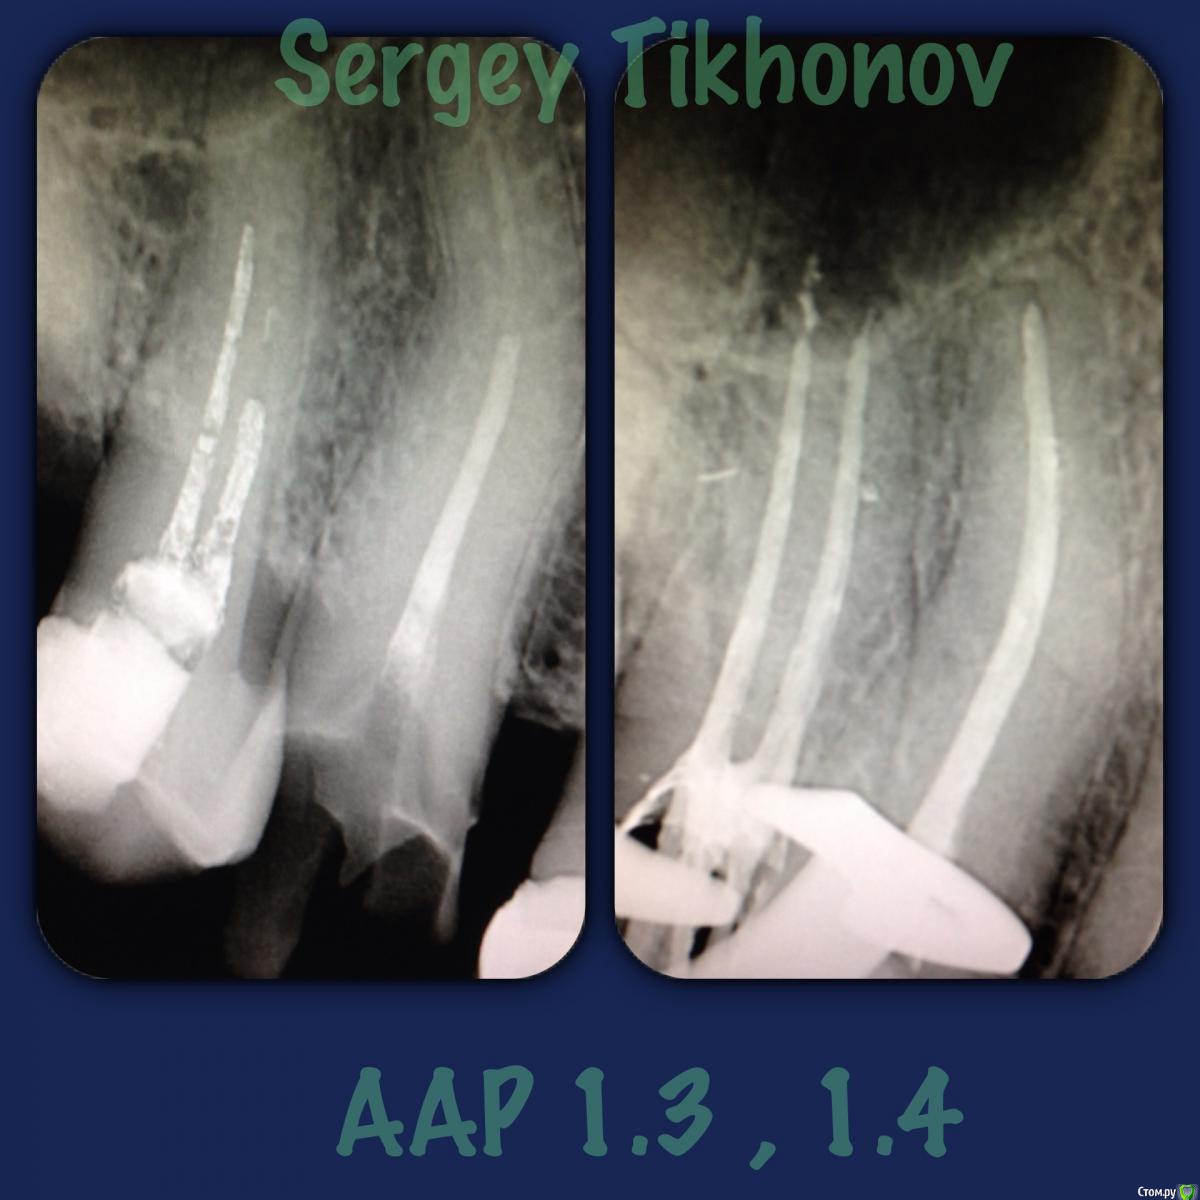

SSTi Опубликовано 28 февраля, 2015 Автор Поделиться Опубликовано 28 февраля, 2015 стандартный аар с пропущенными канальями 10 Ссылка на комментарий